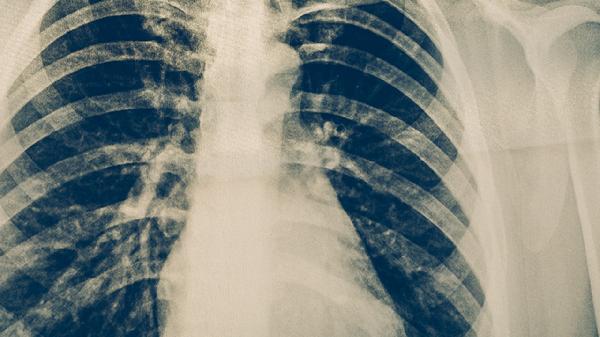

细菌性肺炎早期症状有哪些

细菌性肺炎早期症状主要有咳嗽、咳痰、发热、胸痛、呼吸困难等。细菌性肺炎是由细菌感染引起的肺部炎症,常见致病菌包括肺炎链球菌、流感嗜血杆菌等,患者需及时就医明确诊断。